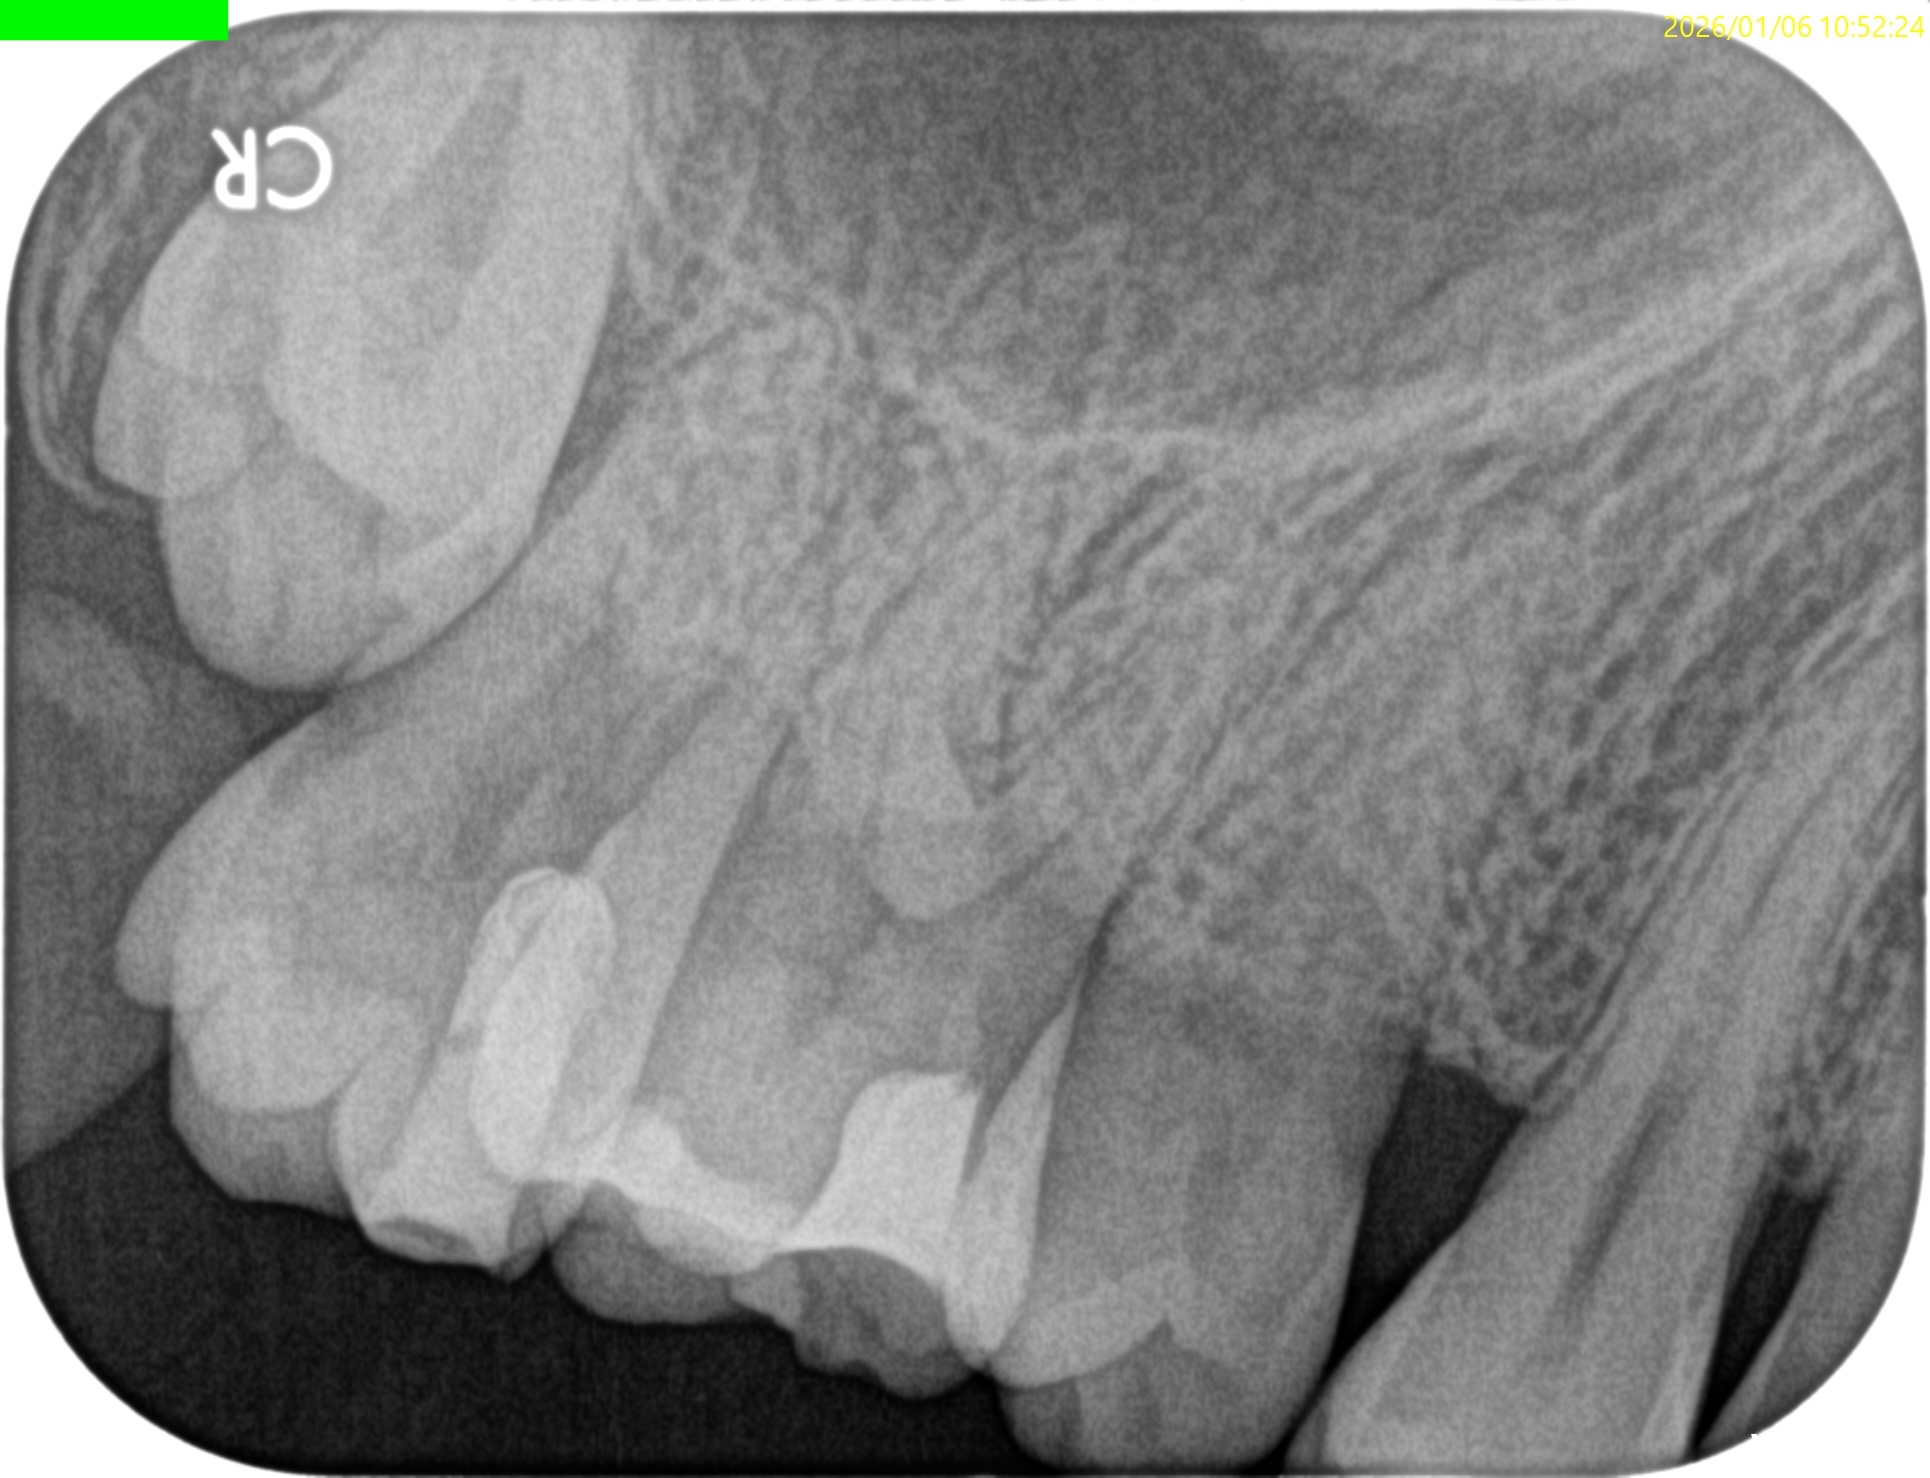

過去治療の経過観察。

1年以上前に, #14 Intentional Replantationを行っていた。

術前にSinus tractがあり、

3根管全てがここまで大きく拡大形成されており、

DBとPがつながっている。上顎第2大臼歯のような第1大臼歯で、

歯根を取り囲むように歯槽骨が溶けている。

垂直性歯根破折が疑われる。

そして、頬側の歯槽骨がほとんどない。

この治療から1.9yr経過していた。

#14 Intentional Replantation 1.9yr recall(2026.1.6)

術前のSinus tractは消失した。

PA, CBCTも撮影した。

初診時と比較した。

問題が劇的に解決していることがわかる。